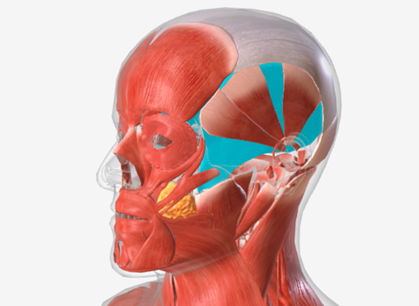

Temporalis

origin is the temporal and parietal bones of the cranium, coursing down and forward through the zygomatic arch, to insert on the coronoid process and the ramus of the mandible; function is to elevate the mandible and draw it back if protruded

Medial pterygoid

origin is the medial pterygoid plate of the sphenoid bone, coursing down and back to the mandibular ramus; function is to elevate the mandible

Lateral pterygoid

origin is the lateral pterygoid plate and the greater wing of the sphenoid, coursing back to the mandible; function is to protrude the mandible